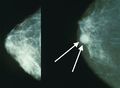

تصوير الثدي يظهر ثدياً طبيعياً (اليسار) وثدياً مصاب بالسرطان (اليمين).

يتضمن الفحص السريري أو الذاتي للثدي تحسس الثدي للوقوف على وجود كتل أو أي تشوهات أخرى. يتم إجراء فحوصات الثدي السريرية من قبل مقدمي الرعاية الصحية، بينما تُجرى فحوصات الثدي الذاتية من قبل الشخص نفسه.[109] لا تدعم الأدلة فعالية أي من نوعي فحوصات الثدي، لأنه بحلول الوقت الذي يصبح فيه الورم كبيرًا بما يكفي ليتم اكتشافه، من المحتمل أن ينمو لعدة سنوات وبالتالي يصبح كبيرًا بما يكفي ليتم لاكتشافه بدون فحص.[110][111] يستخدم فحص التصوير الإشعاعي لسرطان الثدي بالأشعة السينية لفحص الثدي بحثًا عن أي كتل. أثناء الفحص، يتم ضغط الثدي ويلتقط الفني صورًا من زوايا متعددة. يلتقط التصوير الشعاعي للثدي العام صورًا للثدي بأكمله، بينما يركز تصوير الثدي الشعاعي التشخيصي على كتلة معينة أو منطقة معينة مثيرة للقلق.[112]

يمكن أن توفر طريقتا الفحص الأكثر شيوعًا، وهما الفحص البدني للثدي بواسطة مقدم الرعاية الصحية والتصوير الإشعاعي للثدي، احتمالًا تقريبيًا لوجود كتلة سرطانية، وقد تكتشف أيضًا بعض الآفات الأخرى، مثل الكيسات البسيطة.[122] عندما تكون هذه الفحوصات غير حاسمة، يمكن لمقدم الرعاية الصحية أخذ عينة من السائل الموجود في الكتلة لتحليلها مجهريًا (إجراء يُعرف باسم الخزعة بالإبرة) للمساعدة في تحديد التشخيص. يمكن إجراء الخزعة بالإبرة في عيادة أو مكتب مقدم الرعاية الصحية. يمكن استخدام مخدر موضعي لتخدير أنسجة الثدي لمنع الألم أثناء العملية، ولكن قد لا يكون ضروريًا إذا لم يكن الورم تحت الجلد. إن اكتشاف وجود سائل واضح يجعل الكتلة غير سرطانية إلى حد كبير، ولكن قد يتم إرسال السائل الدموي للفحص تحت المجهر بحثًا عن الخلايا السرطانية. يمكن استخدام الفحص البدني للثدي، والتصوير الشعاعي للثدي، والخزعة بالإبرة معاً لتشخيص سرطان الثدي بدرجة جيدة من الدقة.